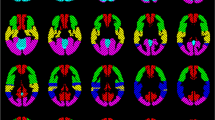

Activation maps of one exemplary subject and one patient with MMD during the identical 9-s BH task were calculated by voxel-wise integration of the signal time course during the time period of the expected maximum signal increase (TTP ± 6 s). The integral values of a time period, in which we did not expect any signal changes, but baseline signal (27–39 s after the end of the BH period), were subtracted. The maps show the integral values of each voxel relative to the mean integral values of the cerebellum. The cerebellum was selected as region of reference, because in patients with MMD, the vessels supplying the cerebellum usually do not reveal MMD-typical stenosis.

As seen in Fig. 7a, the map of one healthy subject showed global symmetrical activation in the gray matter of the whole brain. Distinct BOLD signal increases were detectable in the vascular territories of the ACA, the MCA, the PCA, and the cerebellum, with no relevant differences between the right and left hemisphere (Fig. 8a). The map of the patient with MMD (Fig. 7b) revealed an asymmetric distribution pattern of activated brain regions. Compared with the reference region of the unaffected cerebellum, distinctly reduced activation was measured in some regions of gray matter. Particularly, the vascular territories of the right MCA, where multiple small ischemias were detected, revealed lower activation compared with the left hemisphere. The lower activation in the vascular territories of the right MCA was also evidenced by the reduced signal increase in this region, whereas the signal time course of the left MCA territory showed a nearly normal response curve (Fig. 8b).

Activation map of one exemplary healthy subject (a) and one patient with moyamoya disease (b) during the 9-s BH task calculated by voxel-wise integration of the signal time course. The color bar represents the integral values relative to the integral values of the cerebellum. Breath-hold fMRI of the patient with moyamoya disease showed severe reduction of cerebral reserve capacity in the territory of the right middle cerebral artery (MCA) caused by an occlusion of the right MCA which was only supplied by multiple small collaterals